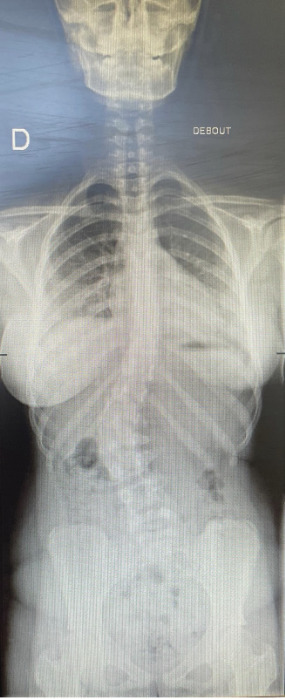

Un bilan radiographique confirme le diagnostic de scoliose, avec un angle de Cobb mesuré à 31° (fig. 1 et 2 ).

Un bilan radiographique du rachis entier debout, de face et de profil est nécessaire. Il permet de mesurer l’angle formé par la tangente de la vertèbre supérieure et de la vertèbre inférieure les plus inclinées (angle de Cobb), ainsi que le stade d’ossification de la crête iliaque, témoin de l’avancée de la croissance (stade de Risser). L’utilisation du système de radiographie EOS, moins irradiant, est à privilégier lorsqu’une surveillance régulière est indiquée.